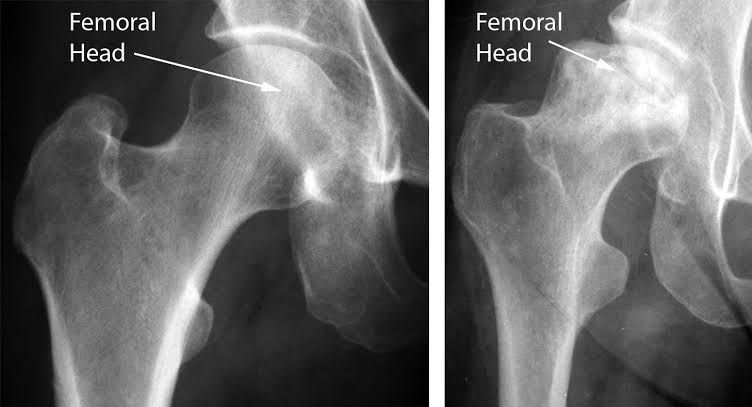

Osteonecrosis

Osteonecrosis, which is also called avascular necrosis (AVN) or aseptic necrosis, is the death of bone cells due to decreased blood flow. It can lead to pain and collapse of areas of bone.